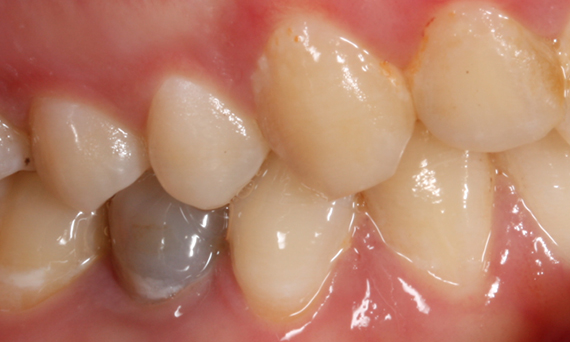

Before: Fractured ceramic restoration made from a leucite-reinforced glass-ceramic after a clinical service time of 12 years.

After: Chairside-fabricated restoration made from an advanced lithium-disilicate ceramic CEREC Tessera.